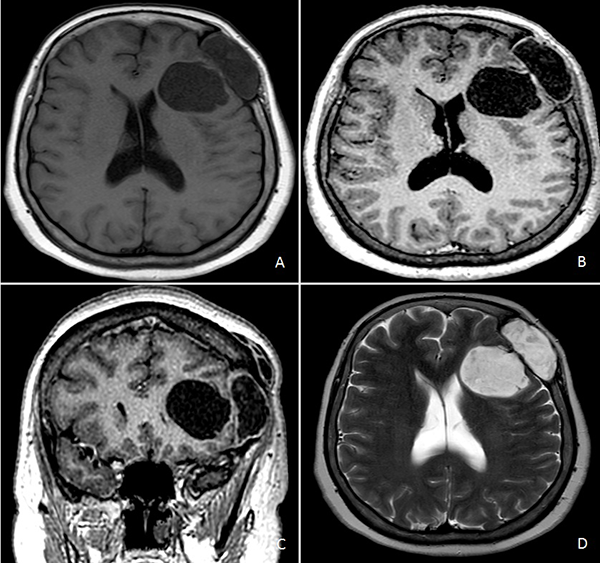

Concurrió con una radiografía (Rx) de cráneo frente y perfil donde se evidenció una lesión radiolúcida, circular y de bordes definidos con signos de remodelación esclerótica (Figura 1A y B). Tomografía computada (TC) de encéfalo mostró una lesión lítica de calota con deformación y esclerosis de la misma asociada a compromiso subgaleal, invasión intradural y extensión intraparenquimatosa en imagen de “reloj de arena” (Figura 1C y D).

Figura 1. A) y B) Rx de cráneo frente y perfil. C) y D) TC de cerebro sin contraste endovenoso.

Figura 2. RM de cerebro. A) Secuencia T1 sin contraste endovenoso. B) y C) Secuencia T1 con contraste endovenoso. D) Secuencia T2.

Resonancia magnética (RM) de encéfalo con contraste endovenoso evidenció una lesión heterogénea, predominantemente hipointensa en secuencia T1, hiperintensa en T2, heterogénea e isointensa con respecto al parénquima cerebral en Flair (Fluid attenuated inversión recovery), con escasas áreas de restricción en la secuencia difusión (DWI) y realce fino periférico tras la administración de contraste (Figura 2). Se observó efecto de masa leve con colapso de asta frontal de ventrículo lateral homolateral. Se realizó una angiotomografía de encéfalo para valorar la vascularización adyacente de la masa y descartar anomalías vasculares, siendo negativa para las mismas.